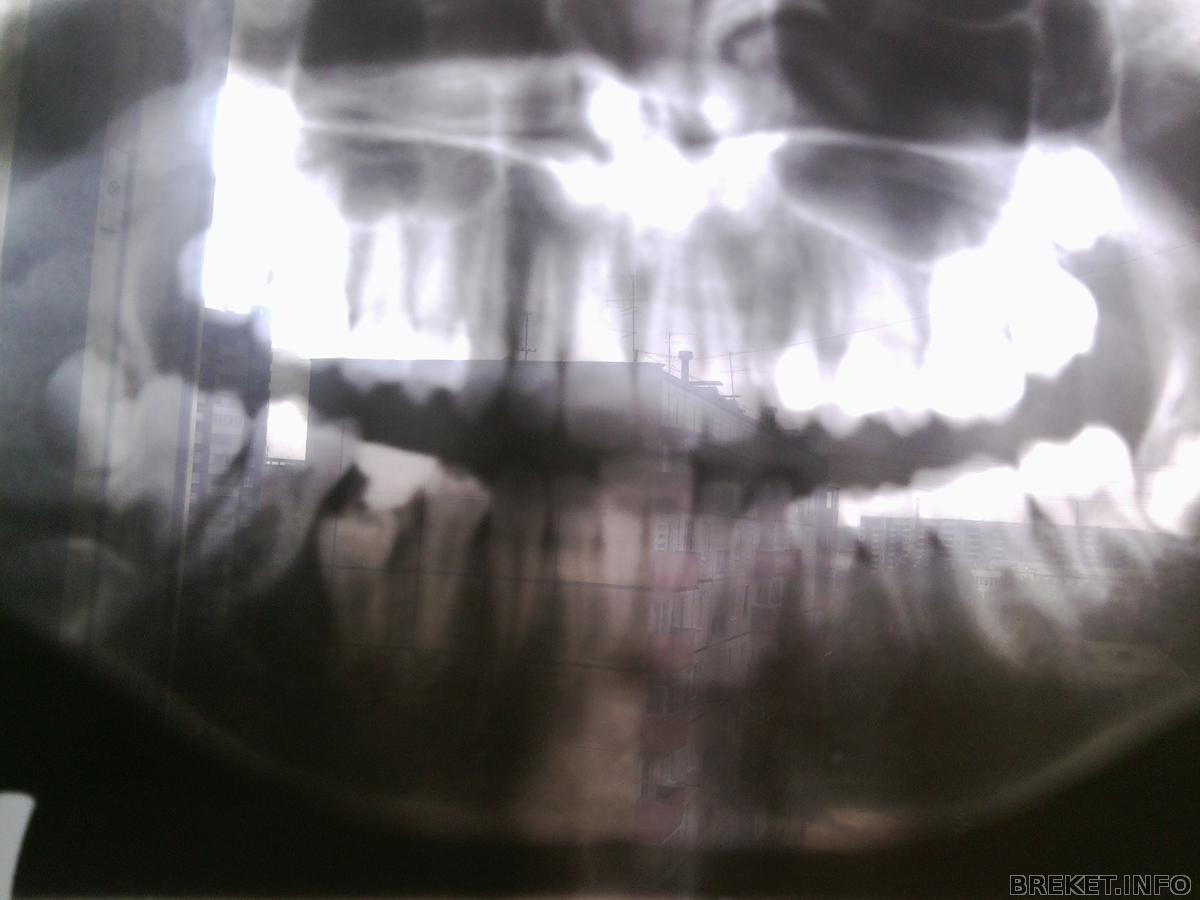

А ещё у меня на нч пятёрка ещё не выросла. Поверх неё молочный зуб растёт. Если его удалить, 5ка может перестать расти. Вот такие вот дела.

А ещ она не ровная и если опять же вырвать молочный зуб, она может подпереть 6ку и та тоже наклонится.

Раз в несколько месяцев приказали делать рентген зубика, чтобы смотреть как он растёт. Ах да, ещё сказали что если выровнять зубы, расстояние между челюстями увеличится.

Вот снимок:

Как думаете, за полгода каналы немного закрылись? Раз сказали приходить через пол года, значит там всё закроется. Но снимок то сделан в декабре! Значит там сейчас побольше закрыто чем на снимке.